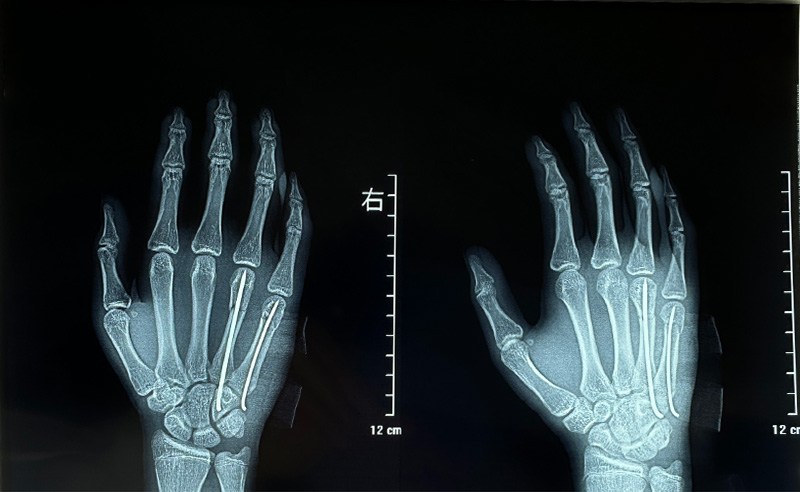

第一个病例是一位13岁的少年。患者因摔伤导致右手第4、5掌骨骨折,入院时右手部肿痛、畸形,活动受限已达30分钟。骨三科团队迅速响应,在神经阻滞麻醉下为患者急诊实施了“右手第4、5掌骨骨折闭合复位内固定术”。术中无需大切口,既精准复位了骨折断端,又最大程度保护了手部功能与外观,为年轻患者的早日康复奠定了坚实基础。

术后